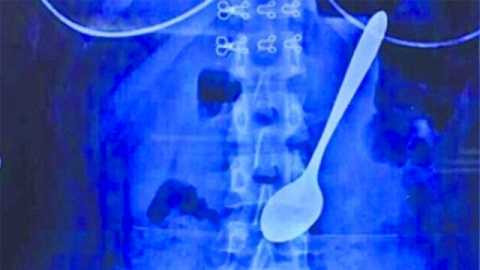

| Chiếc thìa nằm trong dạ dày Weiwei |